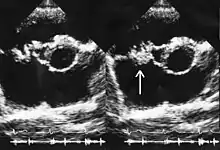

Linezolid's plasma protein binding is approximately 31% (range 4–32%) and its volume of distribution at steady state averages 36.1–47.3 liters in healthy adult volunteers.[2] Peak plasma concentrations (Cmax) are reached one to two hours after administration of the drug. Linezolid is readily distributed to all tissues in the body apart from bone matrix and white adipose tissue.[30] Notably, the concentration of linezolid in the epithelial lining fluid (ELF) of the lower respiratory tract is at least equal to, and often higher than, that achieved in serum (some authors have reported bronchial fluid concentrations up to four times higher than serum concentrations), which may account for its efficacy in treating pneumonia. However, a meta-analysis of clinical trials found that linezolid was not superior to vancomycin, which achieves lower concentrations in the ELF.[99] Cerebrospinal fluid (CSF) concentrations vary; peak CSF concentrations are lower than serum ones, due to slow diffusion across the blood–brain barrier, and trough concentrations in the CSF are higher for the same reason.[18] The average half-life is three hours in children, four hours in teenagers, and five hours in adults.[4]